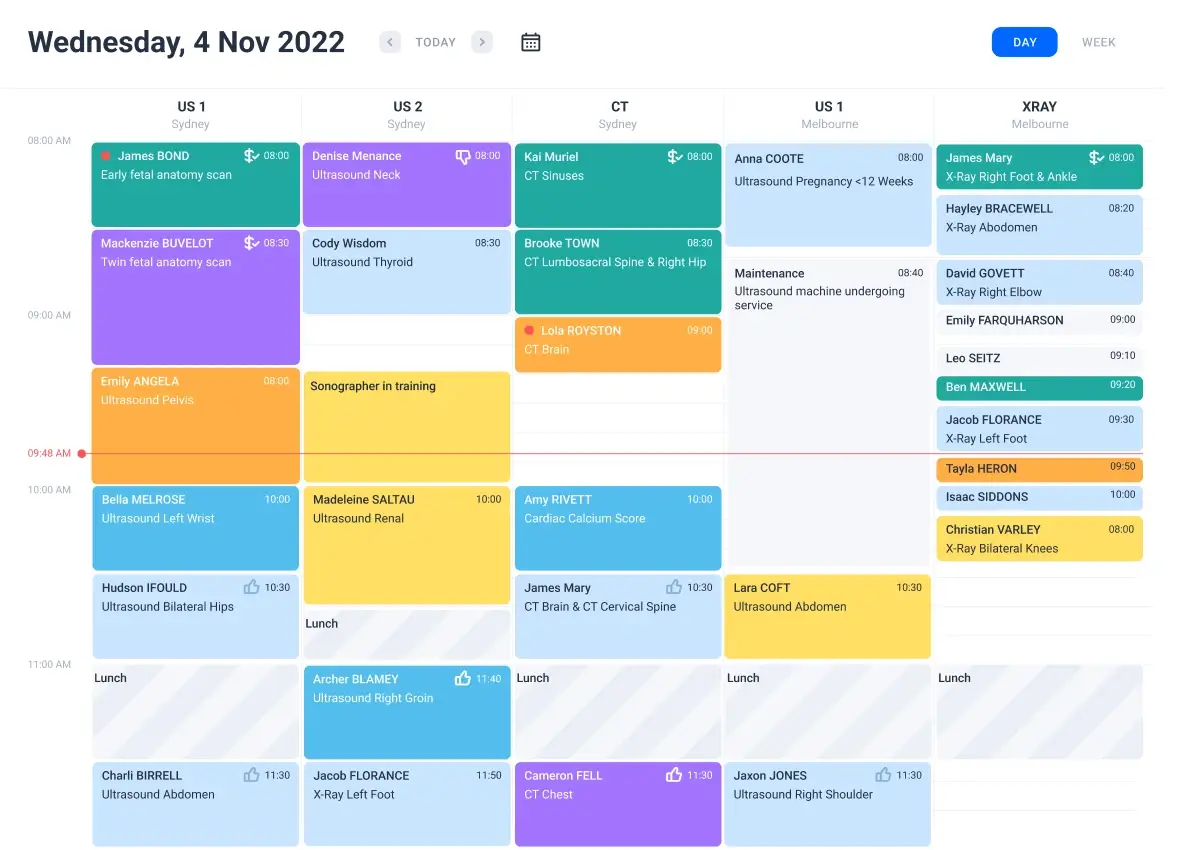

Manage patients and schedule appointments

Shift to automated scheduling with QUBS' cloud-based module, enhancing workflow and patient experience.